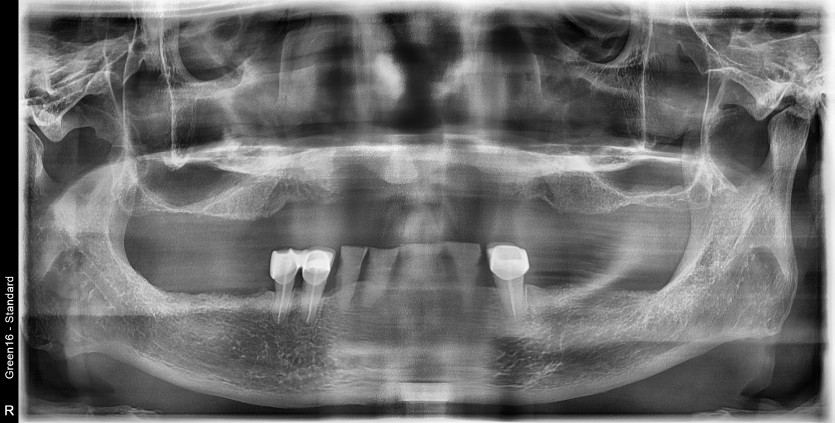

상악 전체 임플란트 / 하악 임플란트 증례입니다.

15개의 임플란트로 완성하였습니다.